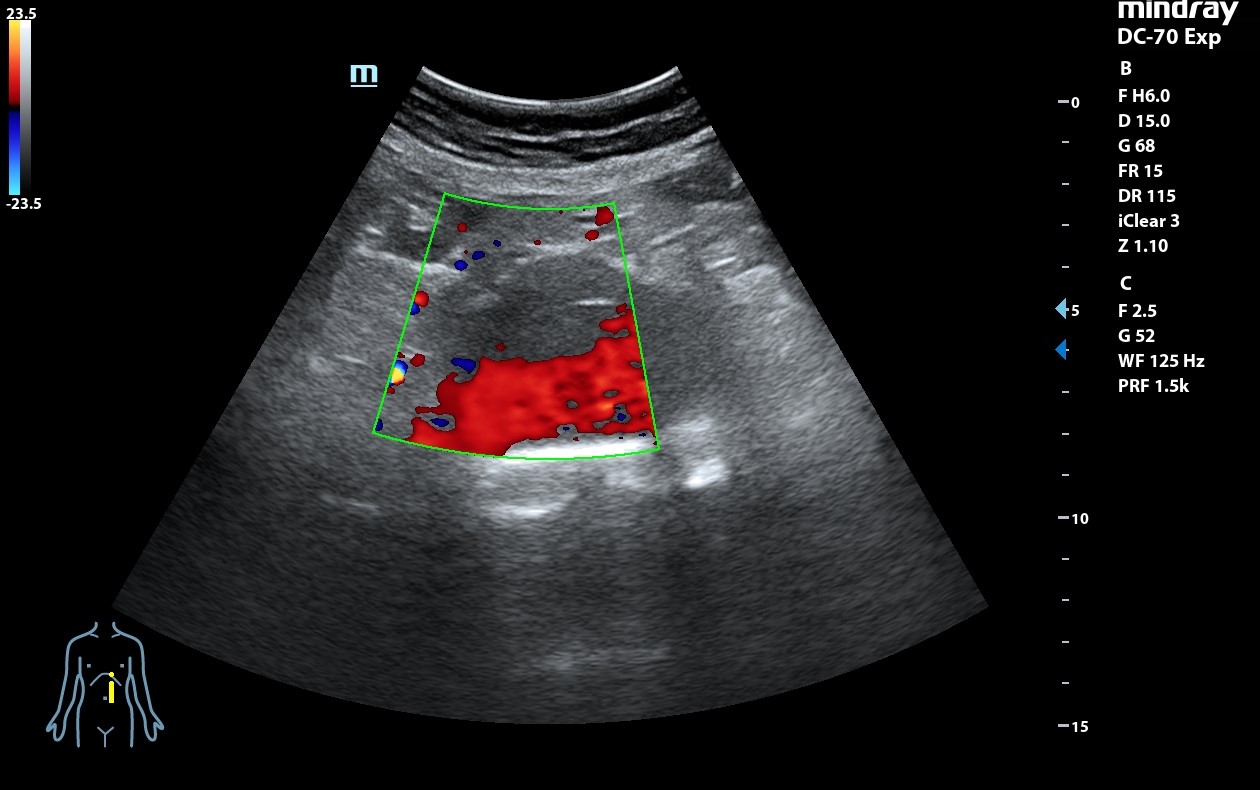

Ecografía clínica: arteria femoral dilatada con material hipoecoico heterogéneo en su pared lateral con un diámetro de 5,85 x 5,88 cm. Dilatación de aorta infrarrenal de 5,1 cm.

Diagnóstico: Aneurisma de arteria femoral derecha. aneurisma de aorta.